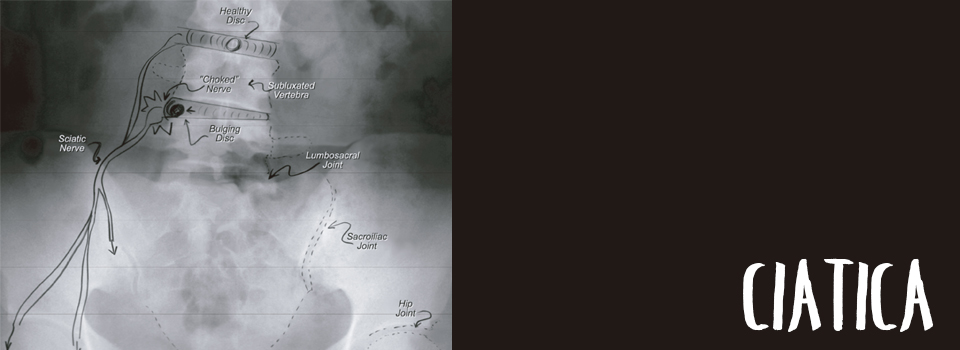

Ciática

El nervio ciático es el nervio más grueso y largo del cuerpo. Algunas de sus ramas pueden ser de más de 91 cm de largo y cubrir cada centímetro cuadrado de los muslos, los glúteos, las rodillas, los tobillos y los pies.

Comúnmente conocida como “ciática”, esta patología sucede cuando uno de los nervios de la raíz es comprimido por un disco protruido o herniado, o es dañado por espolones artrósicos por el deterioro espinal.

Los síntomas pueden incluir “hormigueo”, adormecimiento o fuerte dolor punzante en una pierna, espasmos en el muslo, en la pantorrilla o el pie, dolor de espalda o dolor abdominal.